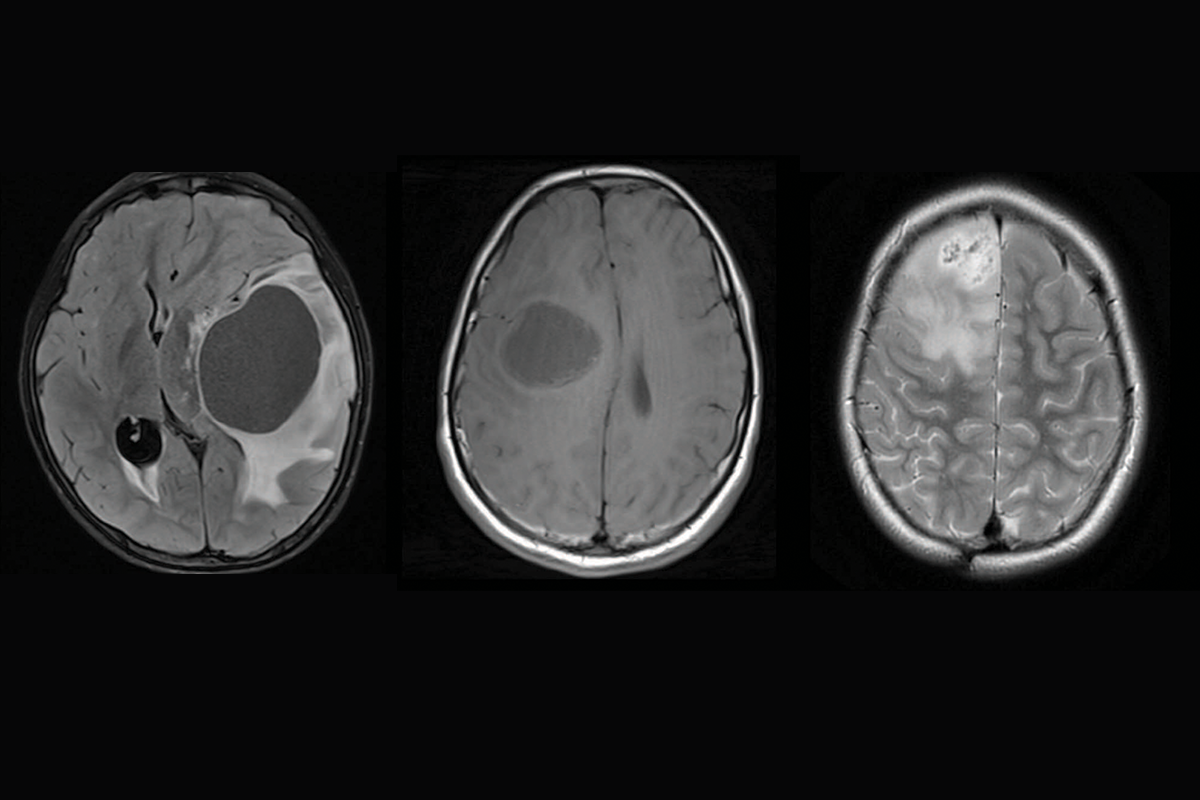

Brain scans showing three different subtypes of priMMRD high-grade glioma.

February 9, 2026

Discovery of unique brain tumour subtypes offers hope for targeted glioma therapies

SickKids researchers identify three subtypes of high-grade gliomas with distinct treatment responses to provide precision care for patients.